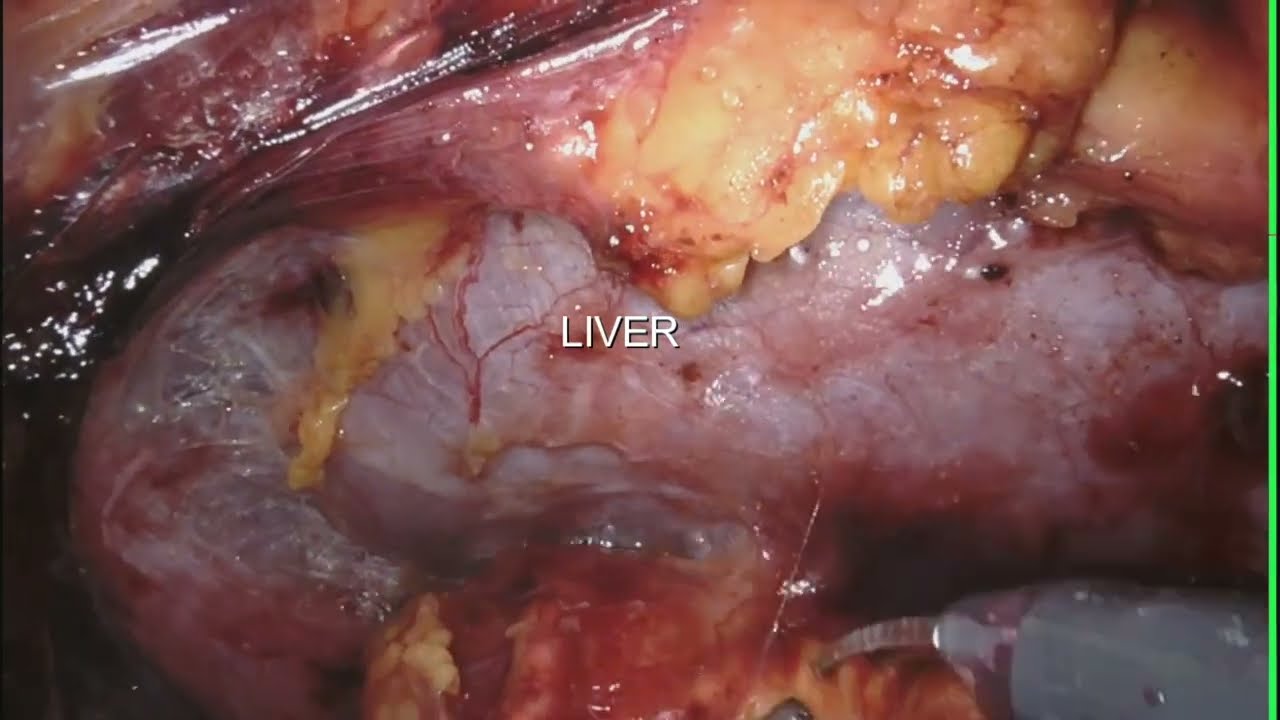

#271 Robotic Right Hepatectomy with Caudate lobectomy for Hilar Cholangiocarcinoma Dr R. Kalayarasan

Robot assisted Left Hepatectomy for HCC